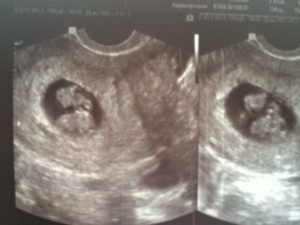

Заметив у себя симптомы, характерные для замершей беременности, обратитесь к гинекологу. Вас направят на УЗИ.

Может ли УЗИ ошибиться при диагностике замершей беременности? Да, может, если его делают на 5 неделе развития плода. В таком случае сердцебиение может ещё не определяться и в норме, тогда врач направит вас на повторное УЗИ через неделю. Рост плодного яйца и появление сердцебиения исключат замершую беременность.

- Последним этапом обследований станет УЗИ. С помощью ультразвукового обследования станет понятно, а бьется ли сердце у эмбриона или нет.

Вторым этапом диагностирования замершей беременности идет УЗИ матки и определение ХГЧ в крови.

В ранних сроках на УЗИ не определяется сердцебиение плода, размеры эмбриона не соответствуют норме или диагностируются анэмбриония (плодные оболочки имеются, а эмбриона нет).

- Ультразвуковое исследование – позволяет выявить наиболее достоверные признаки замершей беременности: отсутствие сердцебиения ребенка, анэмбриония;